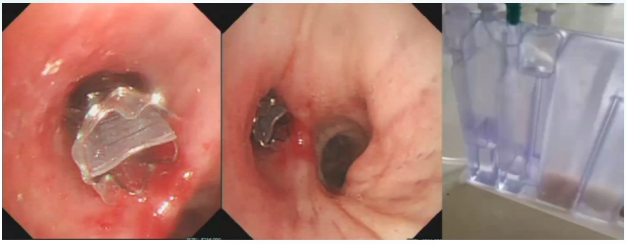

2023年5月8日行气管镜检查:右上叶术后残端改变右中叶支气管炎性改变COOK球囊封堵探查支气管胸膜瘘责任支气管术4

图片

4  气管镜检查(2023-05-08)